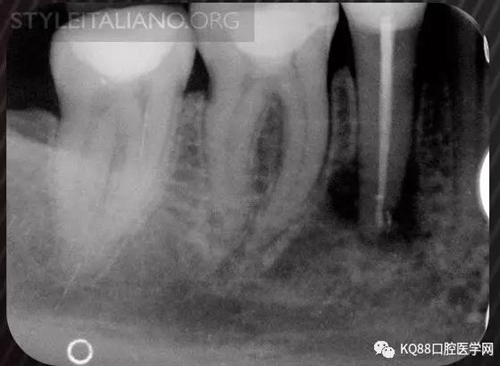

Img. 3 - The frequency of post-endodontic pain is higher in teeth with periapical or periradicular lesions. Infected debris can be forced in the periradicular tissue through a resorpted apex, thus generating acute inflammation. Creating a glide path prior to instrumentation and using a step-down technique can reduce the amount of extruded debris.

Img. 4 - Case 2: This necrotic first mandibular molar was treated in one visit, and the patient complained of post-operative pain. Analgesics and antibiotics were prescribed, and occlusion relieved. Symptoms disappeared after two days, and a radiographic follow-up after two years showed healing of the periradicular lesion.